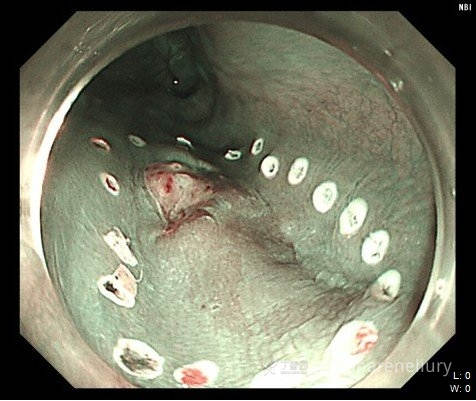

临床诊断:食管早癌

治疗经过:后行ESD治疗,ESD术后病理:

(食管黏膜ESD标本)鳞状细胞癌,中分化;小灶浸润至固有层;侧切缘及基底切缘阴性。

ESD图片: